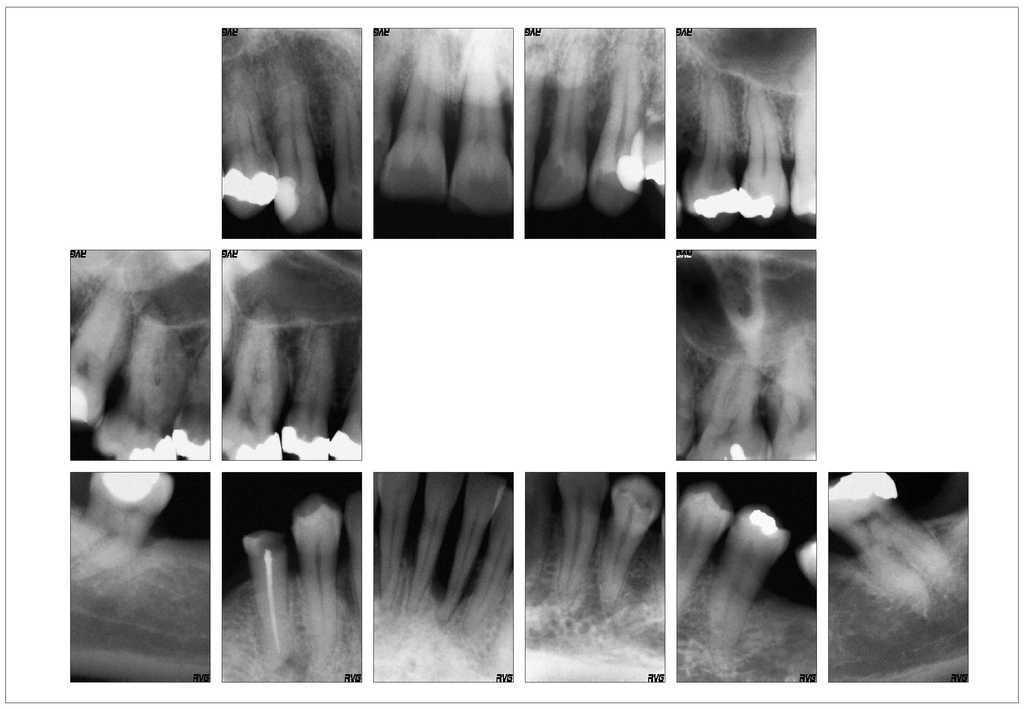

A pesar de que el odontólogo de cabecera había realizado un raspaje a cielo cerrado hacía menos de 2 meses, se observó un absceso periodontal subagudo supurado en los dientes 31 y 21 con destrucción periodontal grave. El diente 31 reaccionó positivamente a la prueba de sensibilidad al frío a pesar de mostrar una pérdida de inserción avanzada en mesial hasta el ápice (profundidad de sondaje [PPD] 11 mm en mesial). El aspecto de la encía correspondía al de un fumador importante: a pesar del grado de destrucción periodontal, la encía mostró un color rosa pálido con una queratinización intensa. El sangrado al sondaje (BOP) estaba muy disminuido como resultado del gran consumo de tabaco y, por lo tanto, se pasó por alto como signo de alerta precoz. Como consecuencia de la elongación secundaria a la destrucción periodontal el diente 21 (PPD 5278) mostraba un traumatismo oclusal. El paciente experimentó una mayor disminución de la dimensión vertical debido a la mesioversión del diente 37. La higiene bucal individual dejó entrever evidentes posibilidades de mejora. En las radiografías se observó una pérdida de inserción horizontal generalizada y vertical localizada (figs. 1 y 2).

Figura 1. Radiografías preoperatorias del 29/8/2006 facilitadas por el odontólogo remitente.